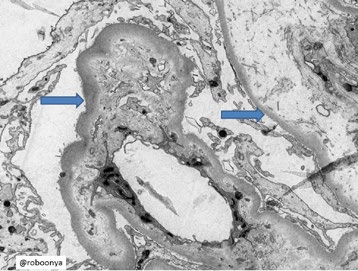

With the rapid development of self-supervised learning (e.g., contrastive learning), the importance of having large-scale images (even without annotations) for training a more generalizable AI model has been widely recognized in medical image analysis. However, collecting large-scale task-specific unannotated data at scale can be challenging for individual labs. Existing online resources, such as digital books, publications, and search engines, provide a new resource for obtaining large-scale images. However, published images in healthcare (e.g., radiology and pathology) consist of a considerable amount of compound figures with subplots. In order to extract and separate compound figures into usable individual images for downstream learning, we propose a simple compound figure separation (SimCFS) framework without using the traditionally required detection bounding box annotations, with a new loss function and a hard case simulation. Our technical contribution is four-fold: (1) we introduce a simulation-based training framework that minimizes the need for resource extensive bounding box annotations; (2) we propose a new side loss that is optimized for compound figure separation; (3) we propose an intra-class image augmentation method to simulate hard cases; and (4) to the best of our knowledge, this is the first study that evaluates the efficacy of leveraging self-supervised learning with compound image separation. From the results, the proposed SimCFS achieved state-of-the-art performance on the ImageCLEF 2016 Compound Figure Separation Database. The pretrained self-supervised learning model using large-scale mined figures improved the accuracy of downstream image classification tasks with a contrastive learning algorithm. The source code of SimCFS is made publicly available at https://github.com/hrlblab/ImageSeperation.